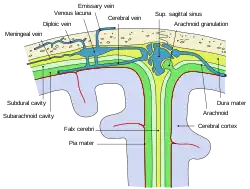

Diagrammatic representation of a section across the top of the skull, showing the membranes of the brain, etc. ("Arachnoid granulation" label is at top right.) | |

Arachnoid granulations (also arachnoid villi, and pacchionian granulations or bodies) are small protrusions of the arachnoid mater (the thin second layer covering the brain) into the outer membrane of the dura mater (the thick outer layer). They protrude into the dural venous sinuses of the brain, and allow cerebrospinal fluid (CSF) to exit the subarachnoid space and enter the blood stream.

The largest granulations lie along the superior sagittal sinus, a large venous space running from front to back along the center of the head (on the inside of the skull). They are, however, present along other dural sinuses as well.

Diffusion across the arachnoid granulations into the superior sagittal sinus returns CSF to the venous circulation.[1]

The arachnoid granulations act as one-way valves. Normally the pressure of the CSF is higher than that of the venous system, so CSF flows through the villi and granulations into the blood. If the pressure is reversed for some reason, fluid will not pass back into the subarachnoid space. The reason for this is not known. It has been suggested that the endothelial cells of the venous sinus create vacuoles of CSF, which move through the cell and out into the blood.